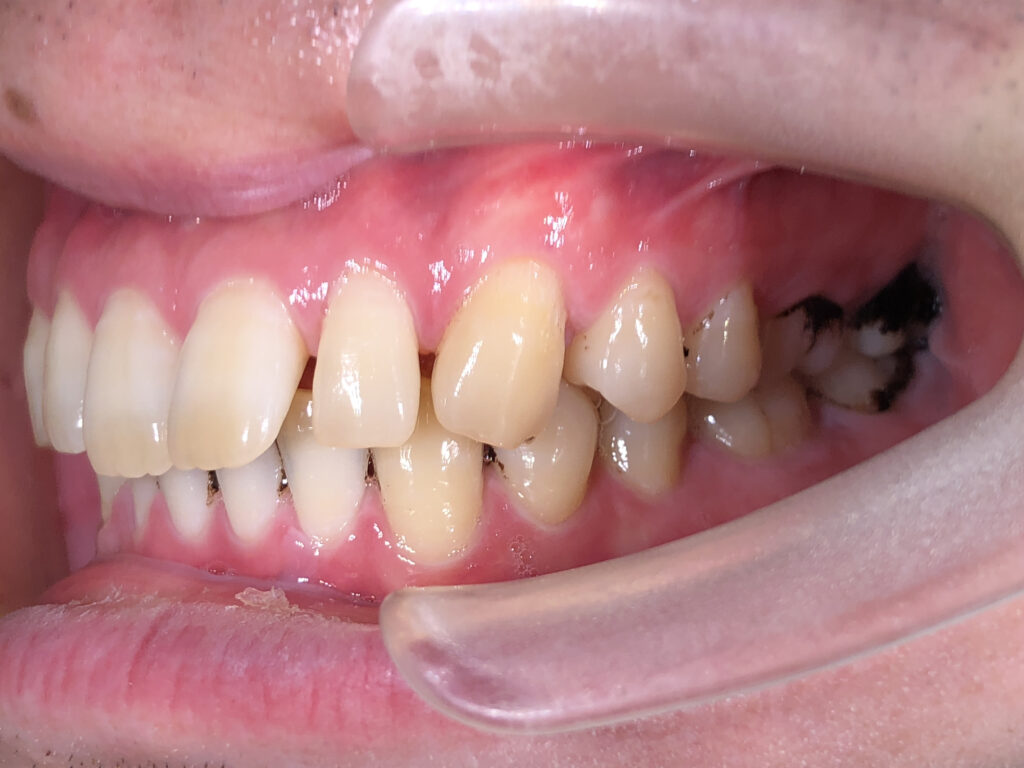

右側

治療前

治療後